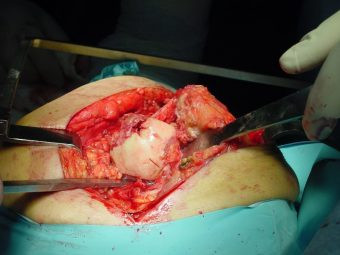

Prótesis Total de Cadera por Fractura

Envíado por Dr. Ricardo Antonio Gómez G.